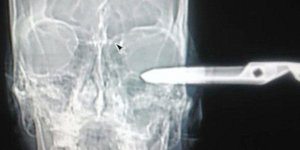

ΚΟΣΜΟΣ 22/01/2015 13:58 Αναυδοι οι γιατροί: Εχω ένα προβληματάκι, ένα ψαλίδι καρφωμένο στο μάτι [εικόνες]